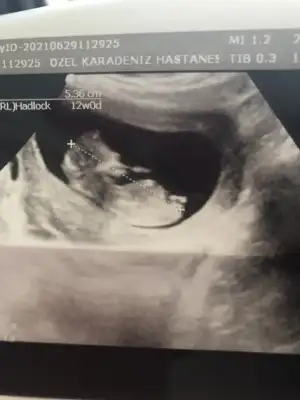

Kıza benzettim canımDoktor bir tahminde bulundu ama bakalım sen ne diceksin![]()

Ya doktorda kız dedi bakalım hayırlısı sağlıklı olsunda 1 aya kesinleşecekKıza benzettim canım![]()

Ya kendi tahminde bulundu muHerkese tahmin yapıyorum, ama benim doktorum nubu görünmeyen ultrason kağıdı vermiş, kendime tahmin yapamıyorum![]()

Yüzde 51 erkek dedi.. pöffff.. ne yapayım ben böyle tahminiYa kendi tahminde bulundu mu![]()